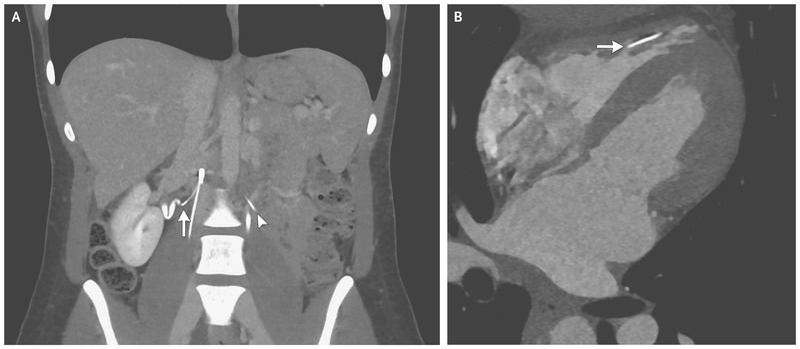

A 28-year-old woman presented to the emergency department with pain in the right flank. Her medical history was notable for nephrolithiasis as well as for deep venous thrombosis and pulmonary embolus that had occurred 10 years earlier and for which she had received an inferior vena cava filter that had not been retrieved. Computed tomography (CT) of the abdomen revealed a fragmented inferior vena cava filter with multiple perforated struts. One strut was approximately 1 mm from the right ureter (Panel A, arrow). Whether this finding was related to the flank pain or was incidental was unclear. Two additional struts had fractured and embolized — one to the left prevertebral space (Panel A, arrowhead) and one to the right ventricle. Cardiac CT angiography revealed that the strut was within the right ventricular trabeculae with no evidence of perforation (Panel B, arrow). The inferior vena cava filter was retrieved with endovascular intervention. The patient’s flank pain resolved with only supportive care before the retrieval of the filter. After consideration of the risks of an intervention to retrieve the struts, a decision was made to leave the embolized struts in place. Fracture of inferior vena cava filters is a potential complication of these devices. At follow-up after the filter retrieval and at 1 year after presentation, the patient was feeling well, and she is being monitored clinically.